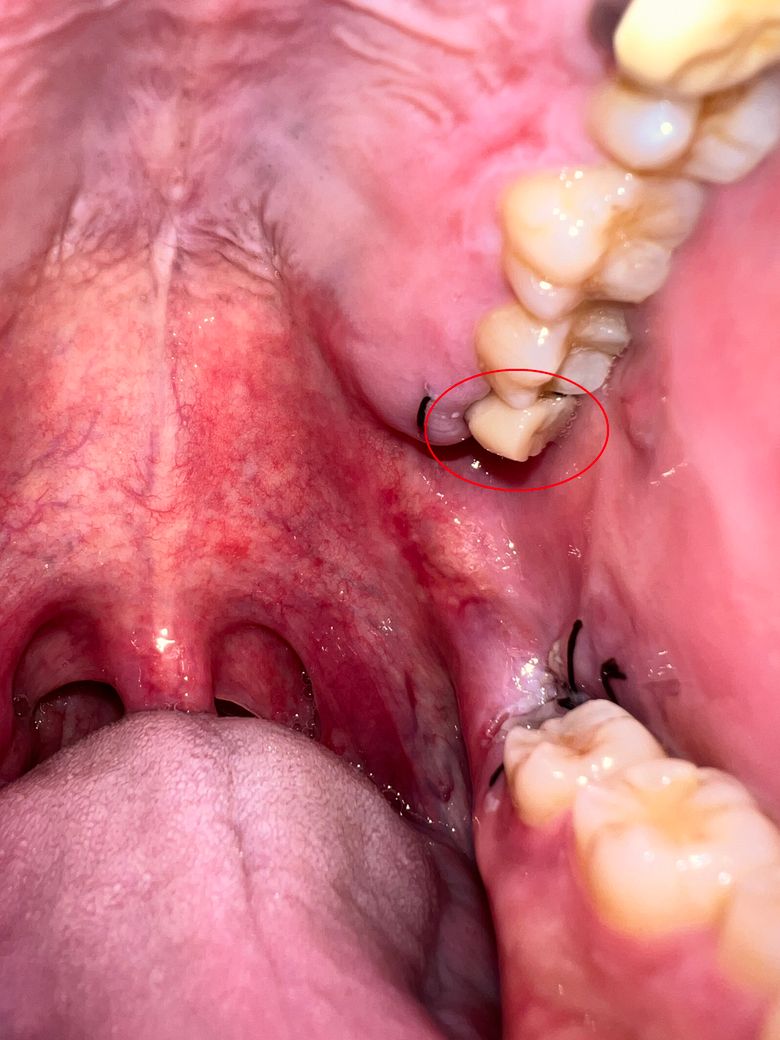

사랑니 발치 후 꼬맨 잇몸 위에 하얀 덩어리?

사랑니 발치 3일 정도 지났습니다.

윗 잇몸 꼬맨 자리에 하얀 덩어리가 이처럼 생겨났는데 혀로 만져보면 말랑말랑 하고 통증은 없습니다.

• 1번 째 사진